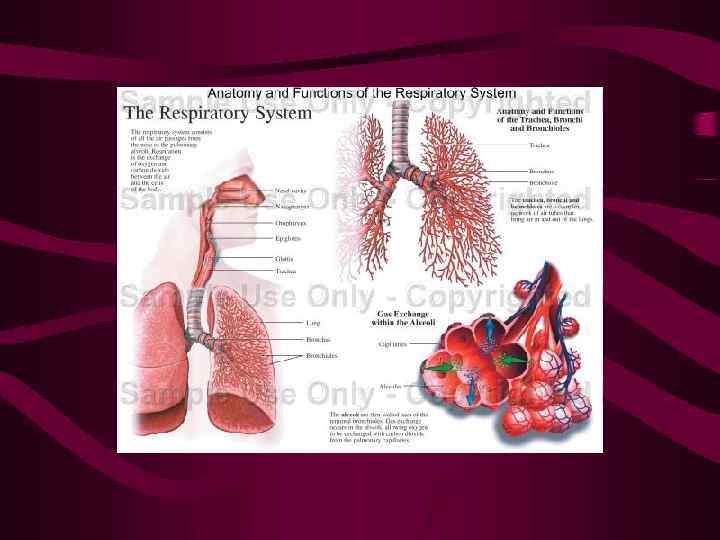

Основная функция легких – газообмен У стоящего вертикально человека имеются три крупных региона в легких: Апикальная зона, где альвеолярное давление чем в артериолах и венулах Средняя зона, где альвеолярное давление чем в венулах, но чем в артериолах, что позволяет циркулировать крови в продолжении части цикла Нижняя зона, где альвеолярное давление ниже, чем сосудистое, позволяющее циркулировать крови по всем сосудам

Основная функция легких – газообмен У стоящего вертикально человека имеются три крупных региона в легких: Апикальная зона, где альвеолярное давление чем в артериолах и венулах Средняя зона, где альвеолярное давление чем в венулах, но чем в артериолах, что позволяет циркулировать крови в продолжении части цикла Нижняя зона, где альвеолярное давление ниже, чем сосудистое, позволяющее циркулировать крови по всем сосудам